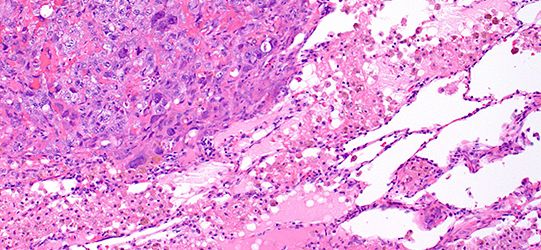

EPITHELIAL MALIGNANT MESOTHELIOMA – Histopathology.guru

EPITHELIAL MALIGNANT MESOTHELIOMA – Histopathology.guru www.histopathology.guru

mesothelioma malignant epithelial histopathology guru cytoplasm abundant nucleoli eosinophilic cuboidal polygonal prominent nuclei